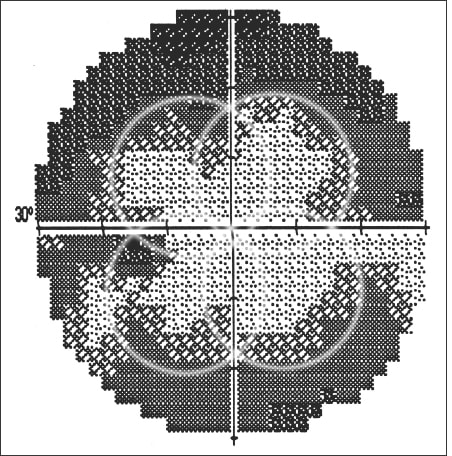

In the extreme, responses are crisp at the four “primary” locations and at the locations immediately surrounding them, which are tested first. The performance starts out well, but the patient gives out before the testing has moved very far from the center. The result is four overlapping circular regions of good thresholds near the center, and seemingly reduced threshold in between, giving a “cloverleaf” pattern on the greyscale (See Figure 2). More moderate progressive inattention may result in milder forms of this pattern that may at first be considered possible results of disease. However, a high FN response rate alerts the attentive clinician to the true cause for the pattern.

Figure 2. Another patient with a normal visual field shown on a subsequent test. On this day, the patient was tired and responded fairly well as the test began within the four circular areas (outlined in white circles), but with fatigue at the end of the test failed to respond to most of the stimuli. The result is a cloverleaf pattern of moderately good visual sensitivity surrounded by poor visual sensitivity.